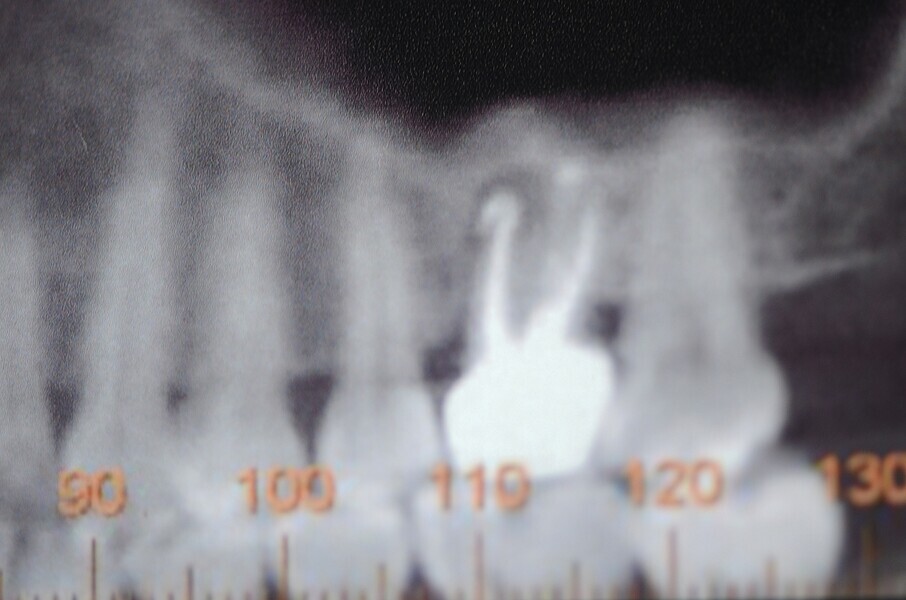

Fig. 1 : Radiographie avant l’extraction (première phase).

Fig. 2 : Radiographie avant l’extraction (première phase).

La première phase du traitement implantaire a consisté à extraire la dent et à préserver l’alvéole au moyen d’une allogreffe et d’une membrane de collagène. Six mois après, l’os régénéré a permis de procéder à la seconde phase du traitement comportant la pose d’un implant deux pièces en céramique (Figs. 1–11).